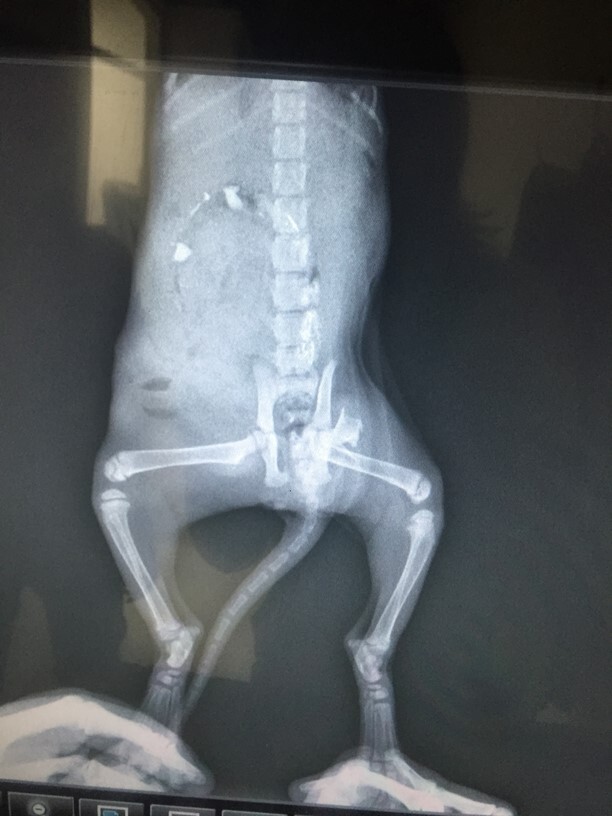

主題: 躲在車底下被不知情的車主移車壓過左後半邊身體的浪貓 申請者姓名: 歐陽妃 花色: 申請日期: 2015-11-04 19:01:53 申請者部落格: 申請者臉書網址: 所在縣市/合作醫院: 高雄市/小新動物醫院 治療費用: 23800元 需求人數: 26人 已結案 (2023-01-18 23:37:19) 報名人員: danielle(已付款)、vopoo(已付款)、SF Chien(已付款)、Stephen(已付款)、嵐羽娘(已付款)、Flower Zhang(已付款)、Lin-Huei Huang(已付款)、Jin Lee(已付款)、Deb Lan(已付款)、Amber Chung(已付款)、sonwing(已付款)、王琇盈(已付款)、nami x2(已付款)、晴天貓咪(已付款)、薇薇安(已付款)、Scarlet x3(已付款)、Moon x2(已付款)、蘇小優(已付款)、Sumi Ho(已付款)、Paula(已付款)、Mimi Chen(已付款)、Eligh Liu(已付款)、 候補人員: 動物病情說明: 經由臉書高雄寵物失蹤認養專區裡的網友,盧嚕咪發求救文,因出事地點跟本人只有距600公尺,到達現場時小貓已被賣地瓜攤販安置在紙箱內,小貓並沒有明顯外傷但後大煺無法正常移動,呼吸有些急迫喘息!據目擊者攤販敘訴車主不知情下將車開出移動,右車後輪就壓過來不及跑出的小貓,當他們撿起小貓就發現小貓上訴的狀況,因為賣地瓜阿姨年長不知如何救援剛好騎車經過較年輕的盧嚕咪小姐發出求教文,獲知訊息馬上到達現場發現小貓肚子腫大左後腿無法行動,呼吸急促!第1站先送銀星動物醫院照X光發現骨折腸子脫落醫院第一時間因人手不足無法急診開刀只好再轉送小新動物醫院才能急診開第1次刀強救小貓維持生命不在讓內出血嚴重腸壁縫合,讓生命穩定後再經過5天後再施行左大腿骨折鋼釘固定,住院修復其內出血及骨折傷勢 動物近況說明: 康復貓已經在11/3出院接回安置,待11/11再由認養人施慧慈小姐接回照顧它一輩子,目前小貓除了左大腿還無法施力外,一切都恢復得很好!也很慶幸可以很快幫它找到認養人